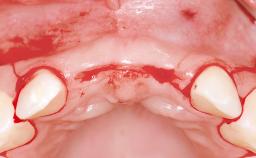

A 38-year-old woman presented with an esthetically unacceptable fixed partial denture replacing teeth 11, 21, 22. She had lost these teeth due to trauma when she was a child. The patient was not in pain but very concerned based on her previous experience that dental treatments had never satisfied her esthetic expectations. She was in good general health and reported no regular medications. No periodontal disease was noted despite the fact that the buccal flange of the prosthesis impeded cleaning of the tooth abutments. The patient did not smoke and complied with home maintenance requirements, as evidenced by her good oral hygiene status.

Bone Volume | Deficient horizontally, requiring prior grafting |